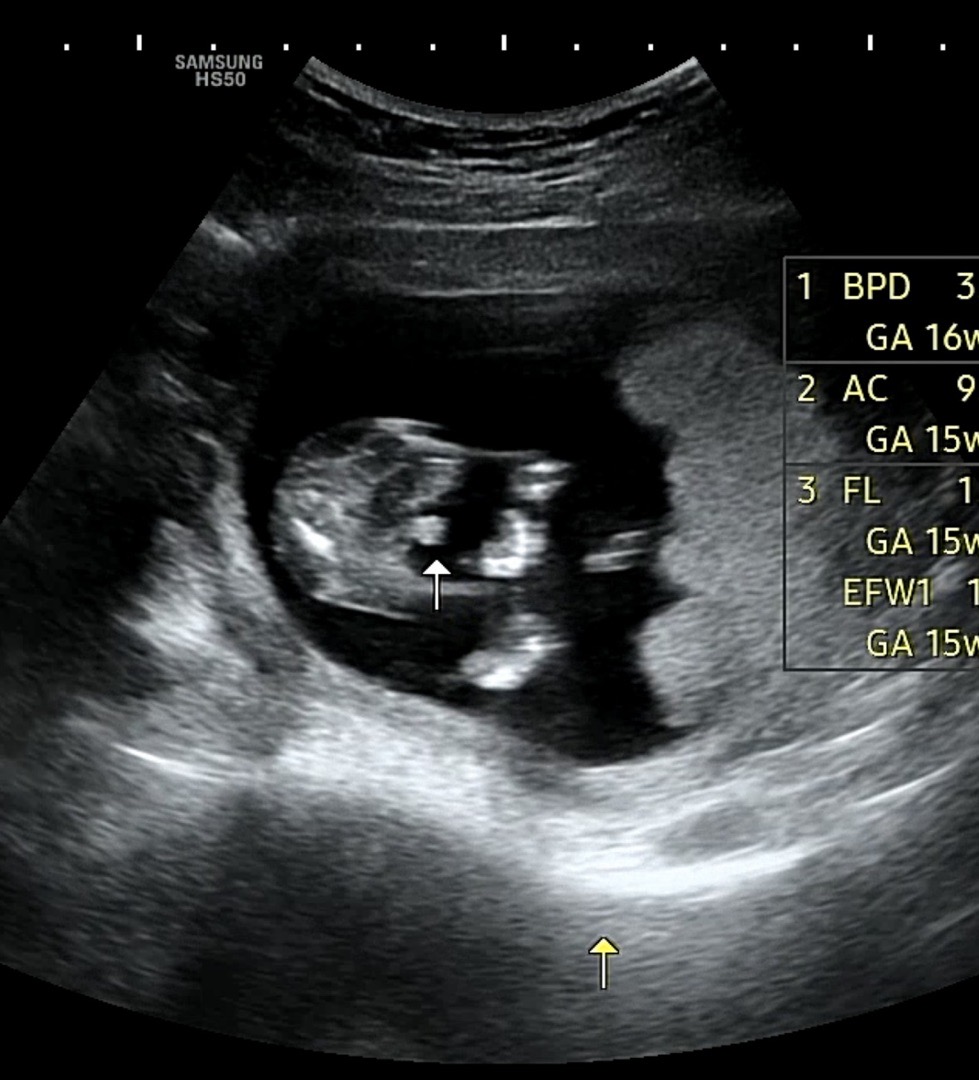

15주 2일이에요! 아들 맞나요?

왼쪽이 엉덩이구 화살표가 꼬추라고 하셨는데 반전없을 시기죠?!